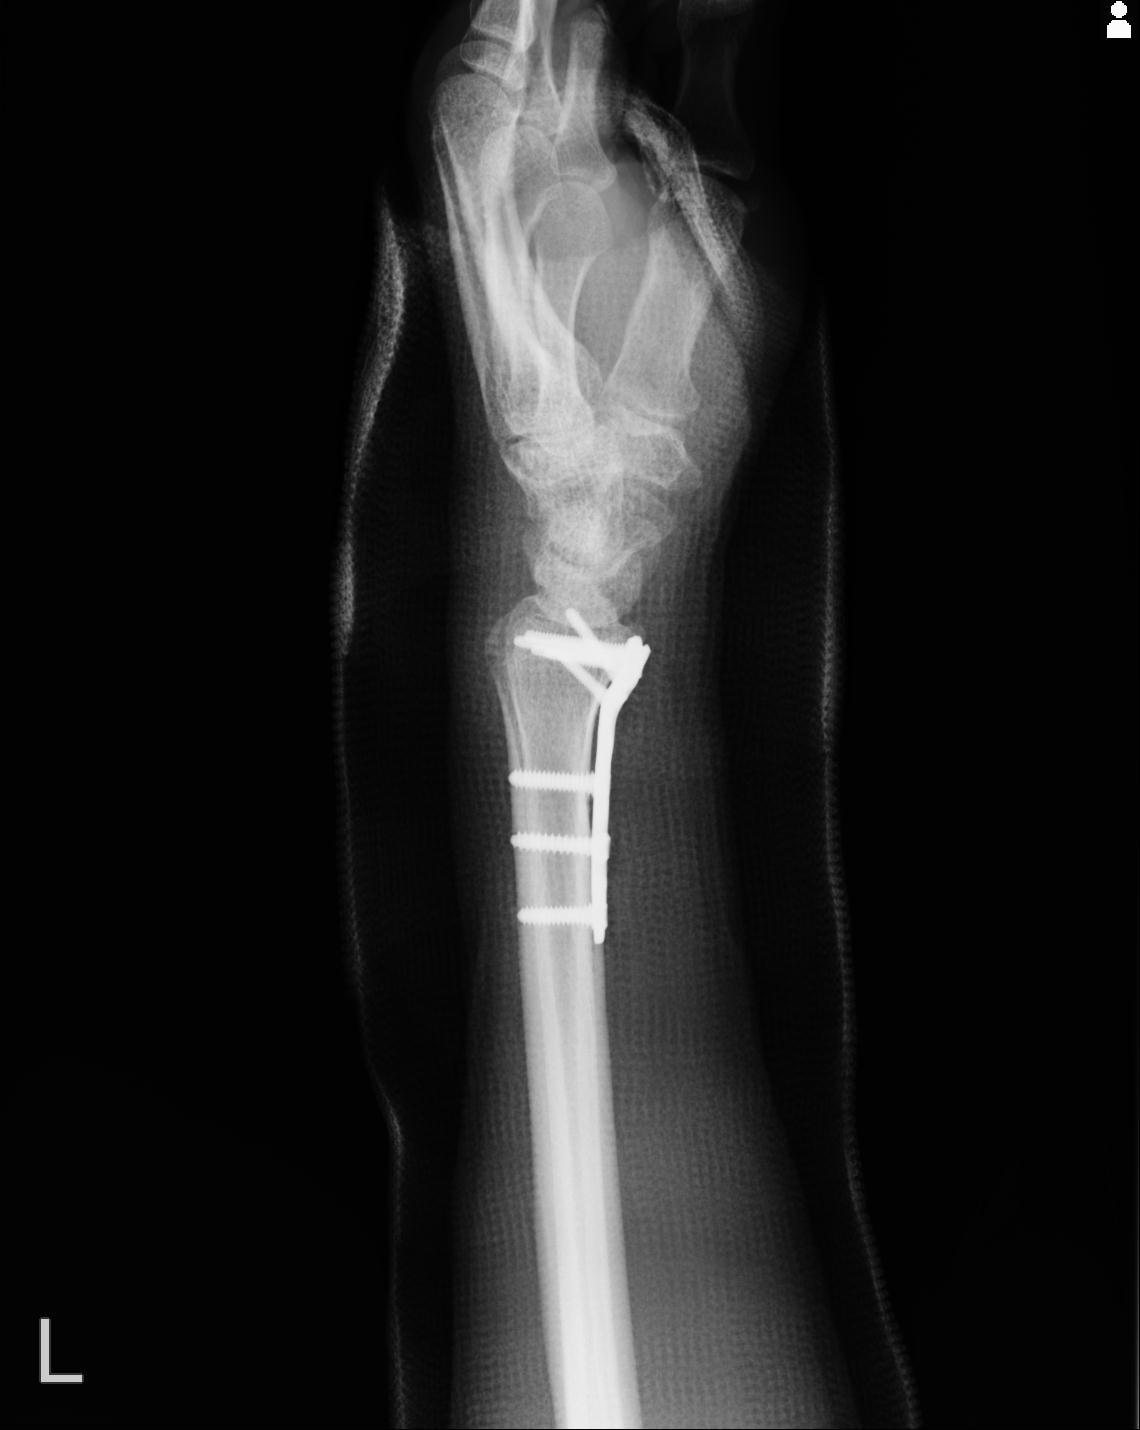

102766 1/5 1/12 左手関節 4R 28歳男性 左橈骨遠位端

110211 1/6 1/8 左前腕 4R 15歳男性 橈骨骨幹部骨折

50435 1/4 1/15 手関節 4R 17歳女性 右橈骨遠位端

102739 12/30 1/5 左手関節 4R 92歳女性 橈骨遠位端

101290 1/4 5/21 5/20 手関節 2R 17歳男性 橈骨遠位端